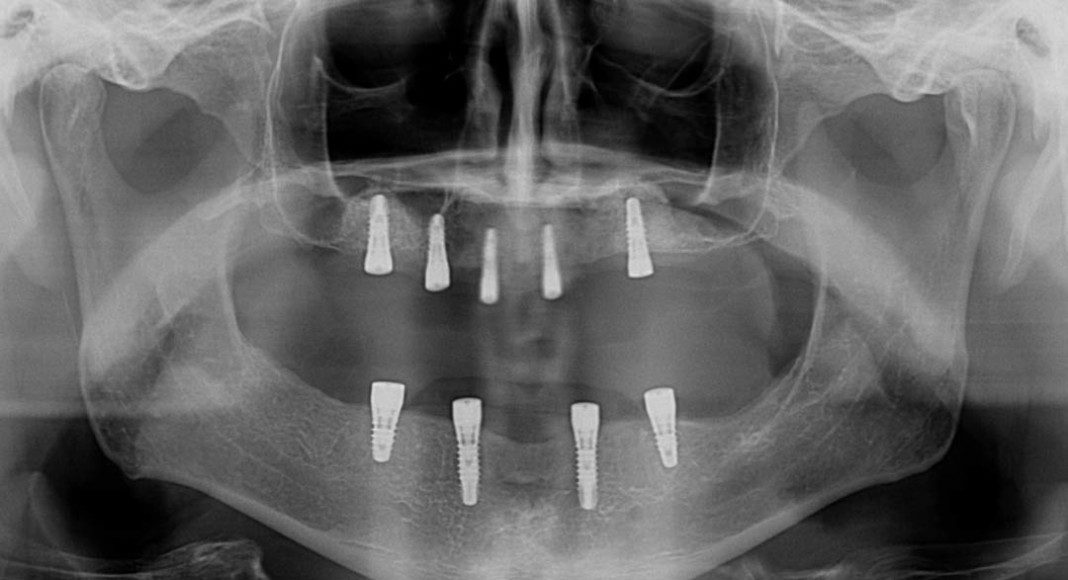

Panoramic x-ray after sinus and onlay bone grafting. Thought subtle, you can see the ping-pong ball size sphere of new bone in the sinuses.